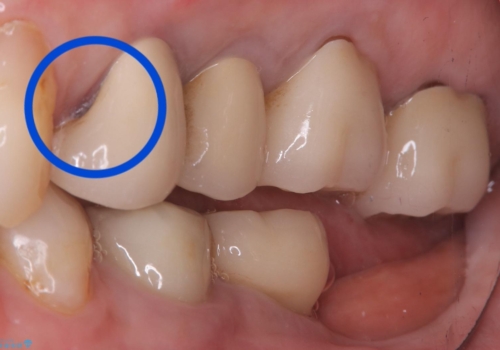

- 主訴:昔入れた被せものの境目の黒いところが気になる

クラウンの不適により境目に汚れが溜まり、黒く見えていました。

適合の良いクラウンへやり替えることとしました。

古いクラウンを除去し、不適部位から中で広がっていたカリエスを除去したのちCRにて築造、仮歯を経てセラミッククラウンをセットしています。